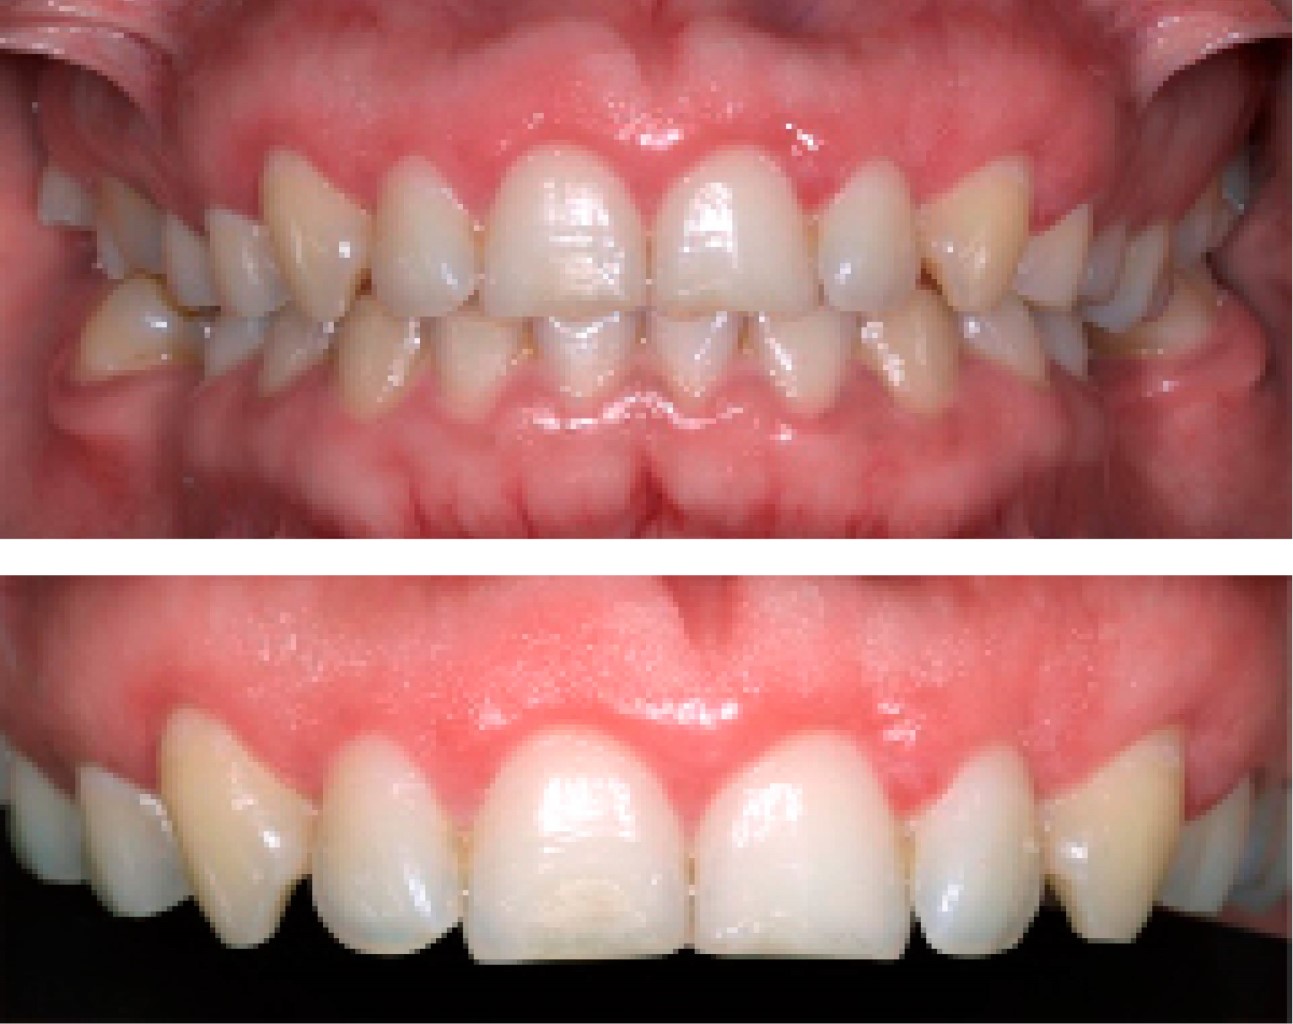

Paciente femenino de 24 años de edad, acude a atención odontológica y manifiesta en su motivo de consulta: "No me siento cómoda con la sonrisa". En la anamnesis realizada no refiere enfermedades patológicas, por lo que se considera como paciente aparentemente sana. En la evaluación clínica inicial se le realiza el sondeo periodontal dando como diagnóstico: erupción pasiva alterada tipo 1, subgrupo B en el sector anterior superior (del 1.3 a 2.3 según nomenclatura FDI) (Figura 1). El plan de tratamiento indicado es alargamiento de corona estético en una sola cita utilizando como herramienta radiológica de apoyo el CBCT con el objetivo de lograr precisión en la ubicación de los siguientes parámetros: tamaño de corona anatómica, longitud de UCE-cresta ósea y cantidad de tejido gingival a eliminar durante el procedimiento quirúrgico.

Se revisó a la paciente tras haber realizar el procedimiento quirúrgico, no presentó ninguna complicación, los tejidos gingivales con características normales, sin procesos inflamatorios y acorde con el proceso de cicatrización (Figura 5).